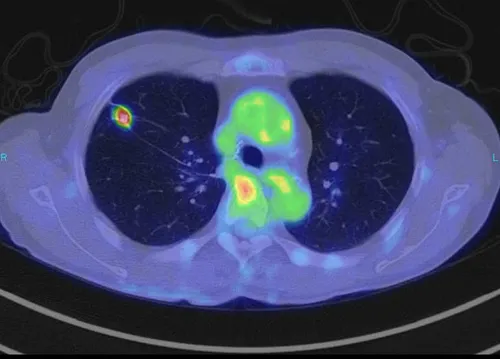

PET-CT検査画像

PET-CT検査画像(右肺がん)